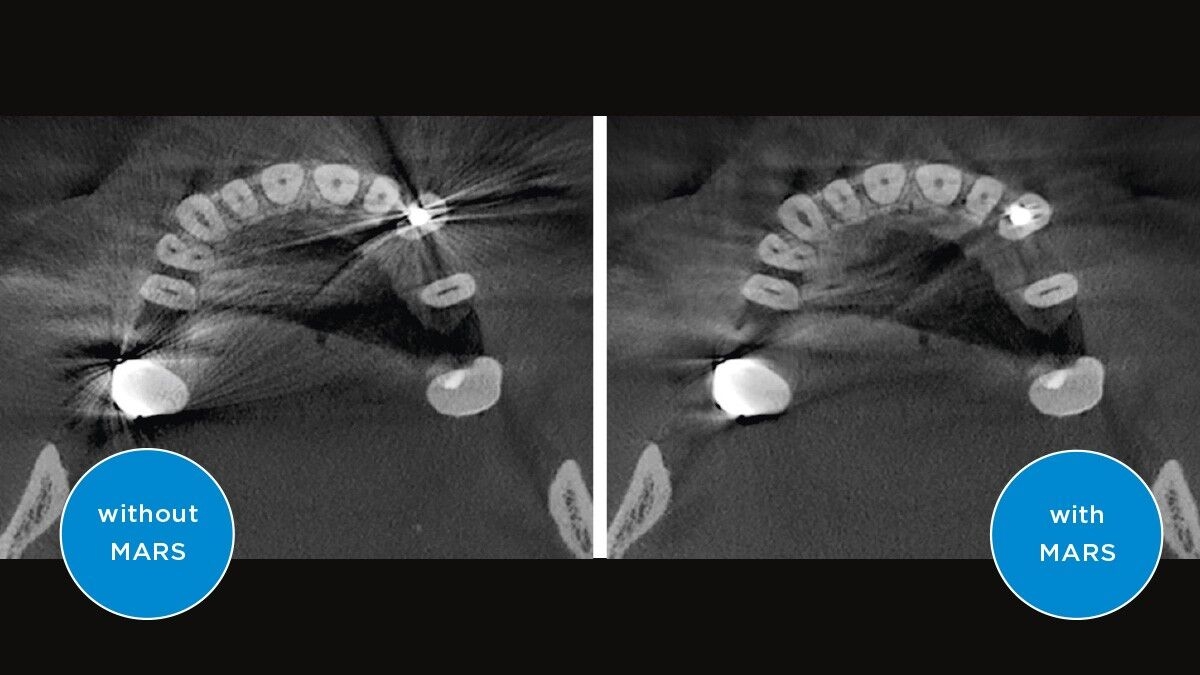

MARS使用创新算法自动检测并减少3D图像中的金属伪影

MARS——金属伪影消除软件

金属伪影是3D X射线成像的一大挑战。在三维重建过程中,不透射线的物体会产生阴影和拖尾效应,从而干扰检查结果。MARS自动减少金属伪影,方便诊断。